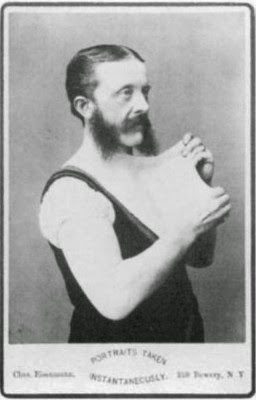

6. Elastický muž

Garry Turner je skutočne pán Úžasný. Narodil sa s Ehlers-Danlosovým syndrómom, čo je stav, ktorý spôsobuje neuveriteľne elastickú kožu, ktorá sa dá natiahnuť ako gumička. No nie je to až také skvelé ako to znie. Garry má neustále bolesti v každom okamihu svojho života. Od chvíle, keď sa zobudí, až do chvíle, keď ide spať. Pociťuje pod kožou neustálu pálčivú bolesť, ktorá bolí tak veľmi, že musí nosiť morfínové náplasti, aby prežil deň. Ďalším problémom je zrážanlivosť krvi, čo znamená, že keď sa poreže, krv sa nedá zastaviť. Berie toľko liekov proti bolesti, že často omdlieva. Jeho neustále omdlievanie mu znemožnilo dokončiť školu, čo vážne ovplyvnilo jeho možnosti. Pracuje ako cirkusový umelec a predvádza svoj stav, ktorý ho trýzni, pred publikom.